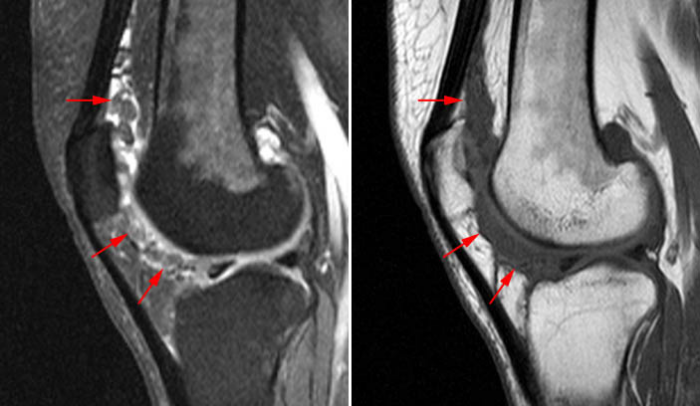

Рисунок 7. У данного пациента гипертрофия и отек надколенникового жирового тела могут быть приняты за древовидную липому. Однако по отсутствию характерного дольчатого строения и явному происхождению изменений из надколенникового жирового тела можно сделать вывод, что это — синдром его ущемления.

Рисунок 7. У данного пациента гипертрофия и отек надколенникового жирового тела могут быть приняты за древовидную липому. Однако по отсутствию характерного дольчатого строения и явному происхождению изменений из надколенникового жирового тела можно сделать вывод, что это — синдром его ущемления.

Рисунок 8. Т1ВИ томограмма пациента с истинной липомой коленного сустава. Сигнал от образования соответствует сигналу от жировой ткани, однако строение его гомогенное, а форма — округлая.

Рисунок 8. Т1ВИ томограмма пациента с истинной липомой коленного сустава. Сигнал от образования соответствует сигналу от жировой ткани, однако строение его гомогенное, а форма — округлая.

Рисунок 9. Древовидная липома локтевого сустава (желтые стрелки) — редкая локализация для данной патологии. Красные стрелки обозначают синовит (с проявлениями пролиферации) сустава, синяя звездочка — выпот.

Рисунок 9. Древовидная липома локтевого сустава (желтые стрелки) — редкая локализация для данной патологии. Красные стрелки обозначают синовит (с проявлениями пролиферации) сустава, синяя звездочка — выпот.